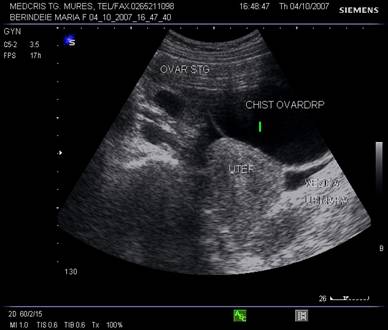

Fig. nr.388. Chist ovarian anecogen , unilocular , cu perete subtire la ecografia transvaginala

Fig. nr.389. Formatiune chistica anteuterina ,aparent partial solida ( inomogena superior ) si partial lichida ( anecogena inferior ) interpusa intre vezica urinara si uter .

Fig. nr.390. Aceeasi formatiune ovariana ca in figura precedenta, la ecografia transvaginala